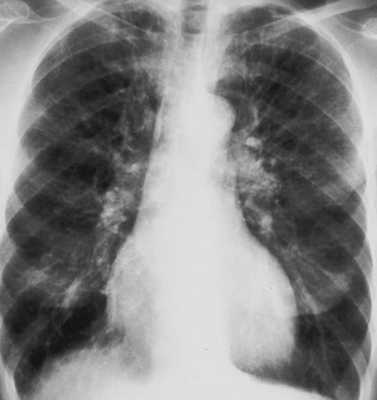

Основные принципы реабилитации для больных с хронической обструктивной болезнью легких

Одним из наиболее распространенных системных дефектов у пациентов с хронической обструктивной болезнью легких является дисфункция скелетной и дыхательной мускулатуры. Поэтому физические тренировки в терапии таких больных играют важную роль. В НИИ пульмонологии ФМБА России созданы специальные комплексы физических упражнений, уменьшающие дисфункцию дыхательной и скелетной мускулатуры и влияющие на гиперинфляцию легких. Такие комплексы включают в себя упражнения на укрепление верхней и нижней групп скелетных мышц, дыхательные упражнения, тренировку дыхательных мышц с помощью тренажеров и высокочастотную осцилляцию грудной клетки.

По последнему определению, озвученному в 2012 г. на совместном совещании по легочной реабилитации Европейского респираторного общества и Американского торакального общества (ERS/ATS), легочная реабилитация сопровождает основные методы лечения пациентов, включает образование, изменение образа жизни пациентов, улучшает физическое и психическое состояние пациента с хроническим респираторным заболеванием и способствует долгосрочному улучшению здоровья [2]. По данным GOLD 2013 г., легочная реабилитация улучшает жизнедеятельность пациента, уменьшает одышку, улучшает качество жизни больных с легочной патологией, сокращает число госпитализаций и дни госпитализаций, улучшает толерантность к физической нагрузке (уровень доказательности А), увеличивает выживаемость и увеличивает бронходилатационный эффект (уровень доказательности В) [3]. Все это говорит о высокой значимости и необходимости проведения легочной реабилитации для больных с ХОБЛ. В НИИ пульмонологии ФМБА России с 2004 г. ведется работа по разработке и применению методов легочной реабилитации у больных с тяжелой дыхательной недостаточностью. К методам легочной реабилитации относятся обучение пациентов, психологическая поддержка, поддержка нутритивного статуса и самая активная часть -- это физическая тренировка.

Дисфункция скелетной и дыхательной мускулатуры является одним из наиболее распространенных системных эффектов у больных с ХОБЛ. Дисфункция дыхательной мускулатуры связана с изменением геометрии мышц у больных с дыхательной недостаточностью, при которой существует дисбаланс между нагрузкой на дыхательные мышцы и объемом дыхательной мускулатуры. Дисбаланс в дыхательной мускулатуре усиливает одышку и приводит к разрыву афферентных и эфферентных связей, которые играют важную роль в регуляции функции легких [4, 5]. Гиперинфляция легких как следствие дыхательной недостаточности приводит к уплощению диафрагмы, такая диафрагма имеет меньшую длину и поэтому развивает меньшую силу и работает в невыгодных условиях с точки зрения механики [5]. Дисфункция скелетных мышц приводит к функциональным и атрофическим изменениям, приводя к снижению силы и выносливости, изменению активности ферментных систем, атрофии. Воздействие воспалительных цитокинов -- фактора некроза опухоли-α (ФНО-α), интерлейкинов ИЛ-6 и ИЛ-1β -- подавляет продукцию анаболического гормона -- инсулиноподобного фактора роста, нарушает дифференцировку и восстановление мышечной ткани, изменяя соотношение миофибрилл 1-го типа (медленных оксидативных) и повышая долю миофибрилл 2-го типа (быстрых гликолитических) [6]. Учитывая развивающуюся слабость и атрофию скелетной и дыхательной мускулатуры у больных с тяжелой формой ХОБЛ, физической тренировке отводится одно из главных мест в терапии.